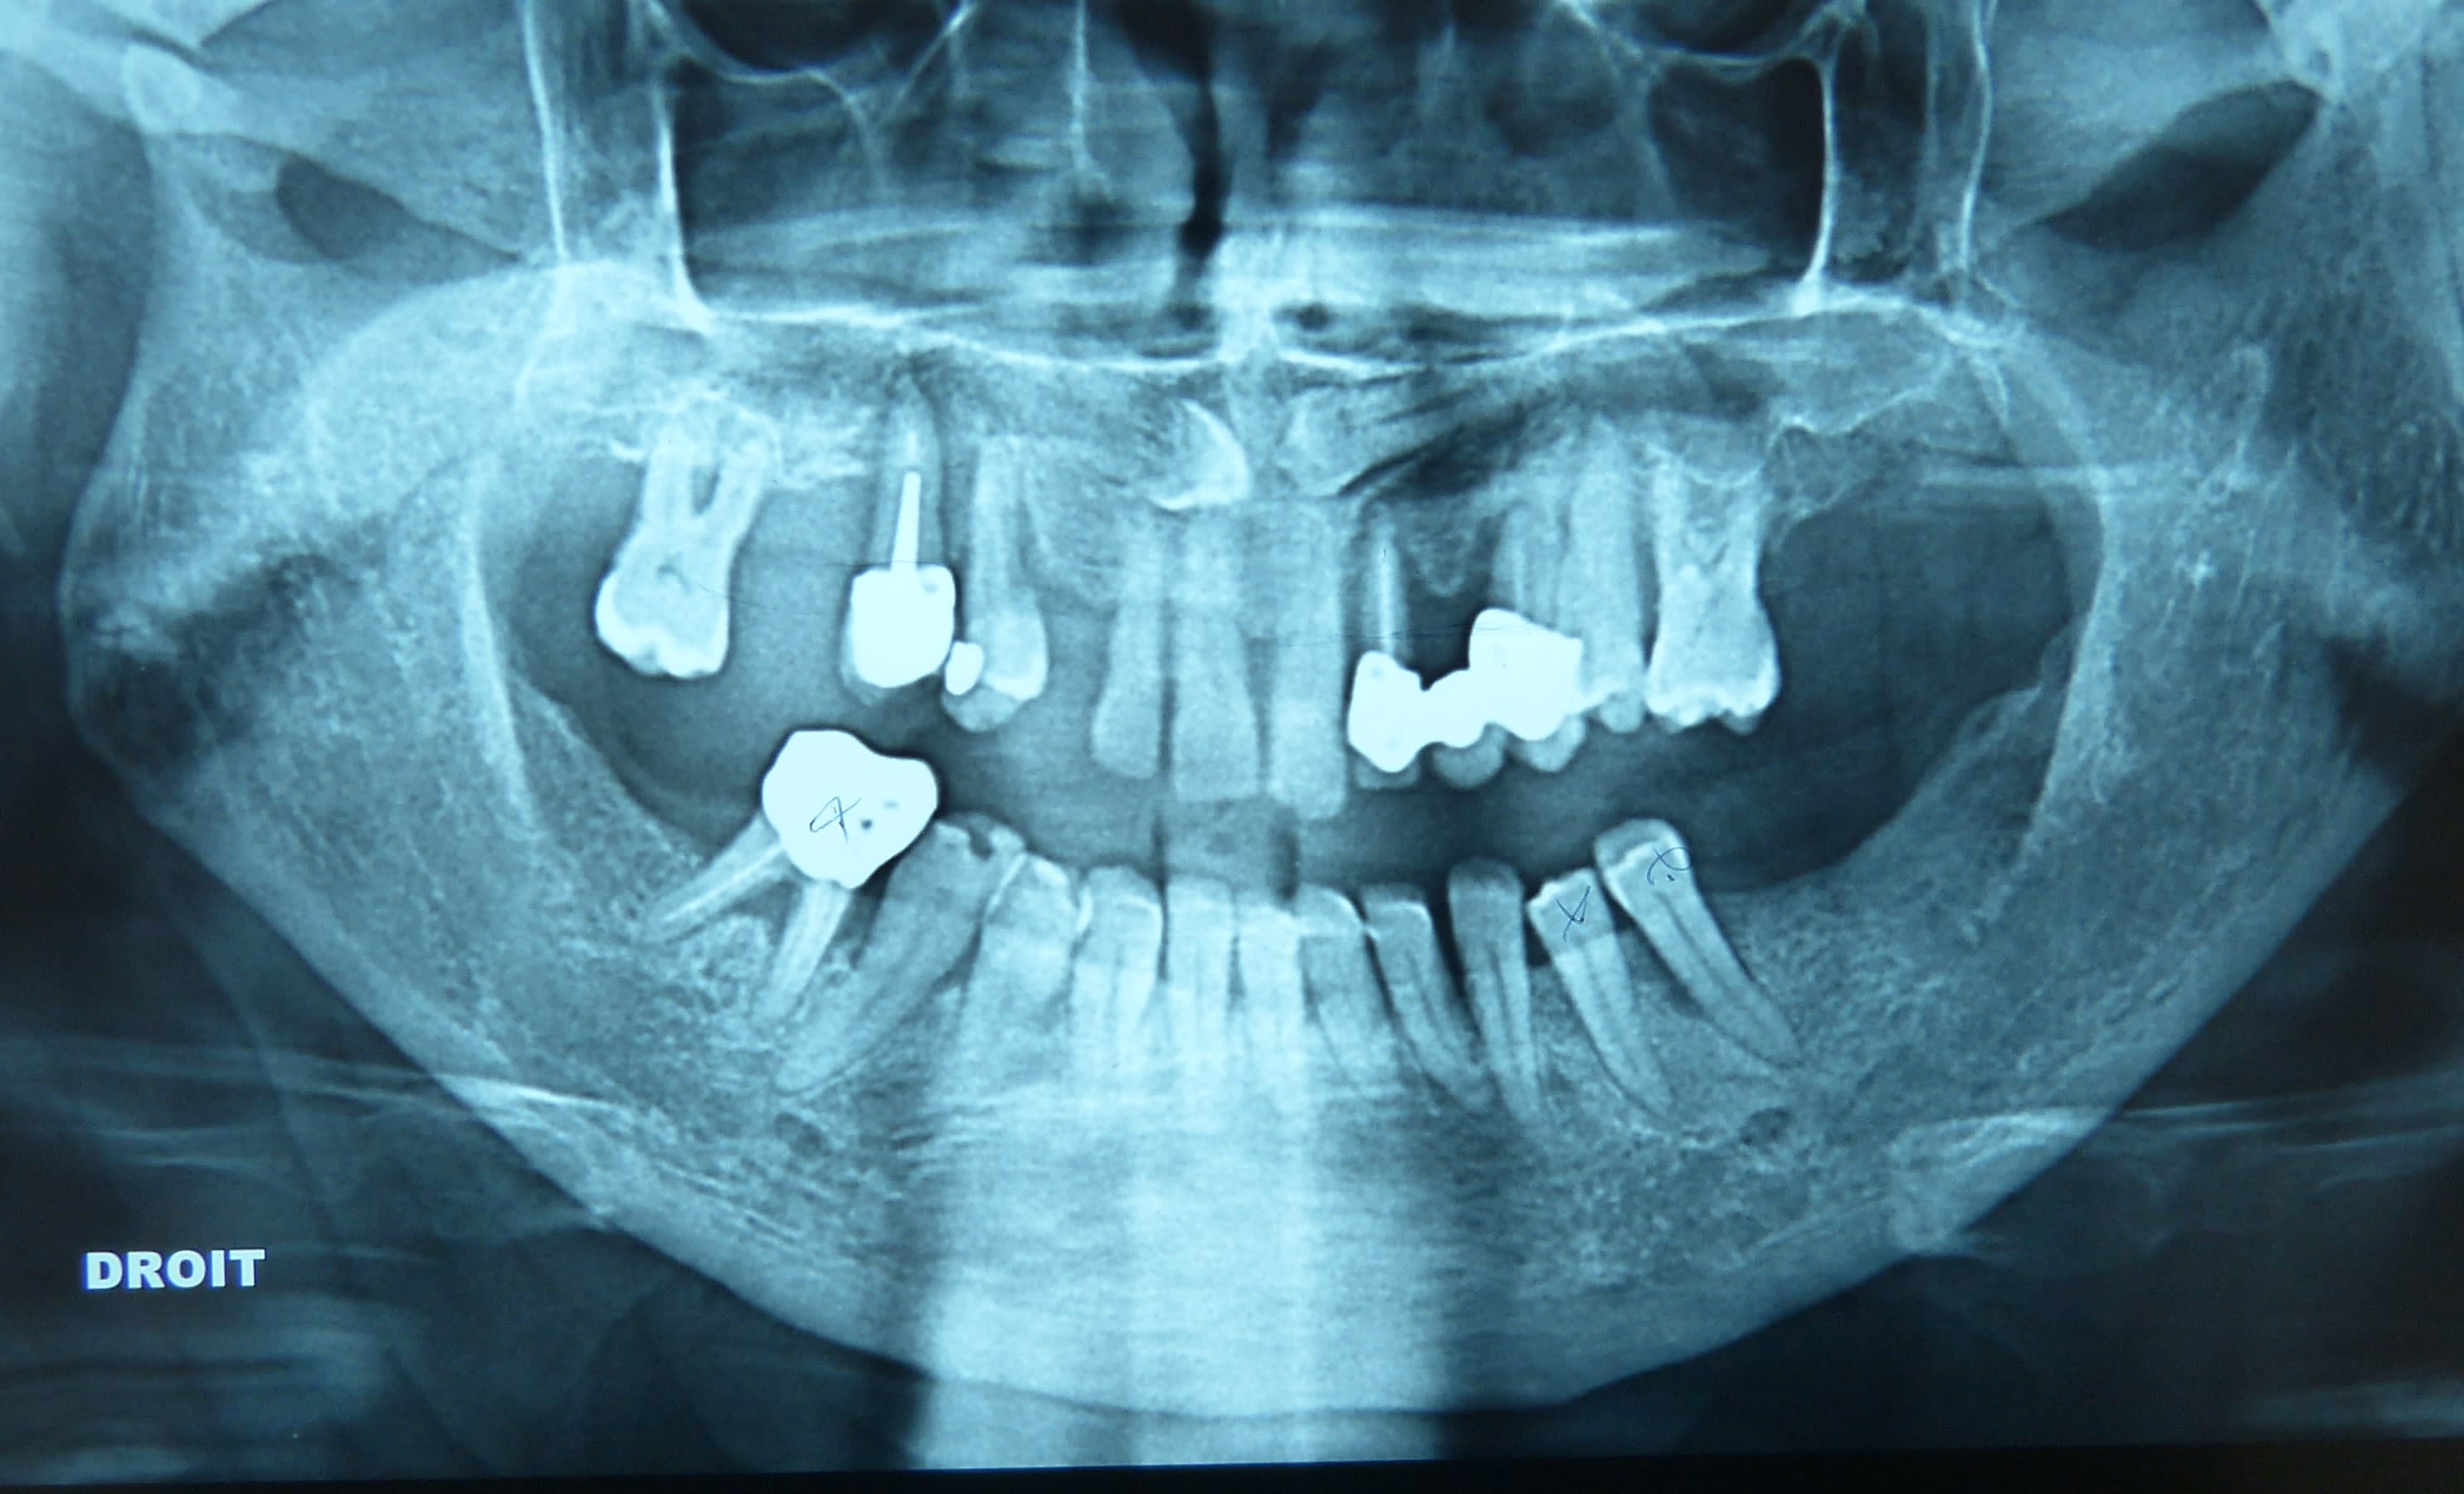

Y en a un qui peut m’expliquer ce qu’est ce trafic ? J’ai trouvé un truc en or sous une couronne

année 80 . le top des ic

oui, on les rentrait à la masse, à démonter c'était impossible. 80 tu dis? Bah pourquoi la racine a pas cassé, il à raison Junior, c'est quoi ce trafic, il aurait 37 ans, ça va à l'encontre de toutes les croyances universitaires.

Moi je ne comprends pas . Pourquoi mettre un IC or sous une CCM

- 12 à extraire

- extraction

- 13 je retire la CCM

- oh putinnn surprise du chef : de l’or dessous ! C’est quoi ce délire encore ! Ces vieilles branches m’auront tout fait !

- bridge provisoire

Avec 1IC en or l etancheité etait top , et aucun risque de fracture radiculaire .

Par dessus tu mettais une ccm chappe or blanc ou civ or jaune

sinon pour moi c'est une ex Richmond or/résine qui à été retaillé dans la masse pour faire un moignon pour une CCM.

Tu démonte la CCM et tu te retrouve avec un truc bizarre mi or mi oxyphosphate.

T’as peut être raison car quand j’ai retouché au moignon , on voit des zones où y a du ciment

Ça ressemble plutôt à une vieille richmond en or qui a été retaillée pour éviter la galère de la dépose.

Je le fais parfois s'il n'y a pas de pathologie apicale et chez les patients âgés.